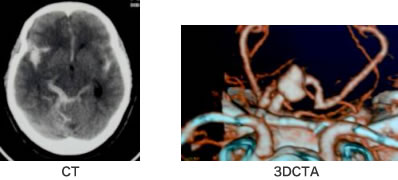

意識や症状のほか、最も診断に役立つのは断層写真CTです。断層写真でくも膜下出血を認めた場合、引き続き出血源の確認のために脳血管撮影やMRA、3D-CTAなどが行われます。